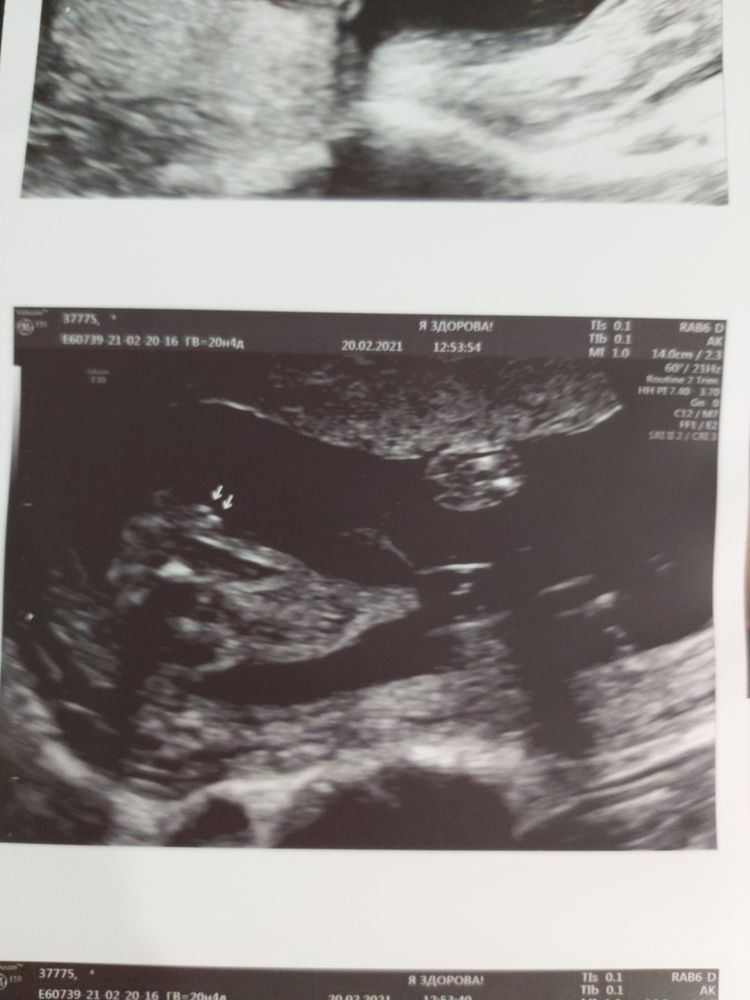

ЭкваторДевочки, приветик! Сегодня нам 20н6д, предыдущие полторы недели выдались для меня очень тяжёлыми в эмоциональном плане. Я наблюдаюсь в платной клинике и бесплатно в жк ПЦ. Так вот обычно перед плановыми скринингами в жк я прохожу скриниг там, где наблюдаюсь платно. В этот раз не было волнения перед вторым скринингом, я шла спокойно и была уверена, что всё хорошо, но не тут то было. Вышла вся на нервах, нам поставили увеличение боковых желудочков в голове, сказали по верхней границе нормы, 8 мм, но врач сразу сказал, что ничего говорить не будет, будем наблюдать в динамике, переделать узи через 2 недели, плюс говорит взвеси есть, решили взять мазок из влагалища и цервикального канала, посев, и фемофлор, инициатива была моя, врач согласился. Делали узи на сроке 19н3д(это 12 февраля было), интернет зло, но я конечно полезла читать, начиталась такого, что плакала постоянно, ждала результатов анализов, и очередного узи. Скрининг в пц был назначен на 19 февраля, срок там 20н3д, меня трясло перед узи ужасно, зашла, легла и жду вердикта, врач сделала замеры и говорит, что с вашей малышкой всё хорошо(про платное узи я ей не сказала) и тут меня прорвало, я так разревелась. Вот почему мы беременные в плохое всегда сразу верим, а в хорошее с трудом? Они меня еле успокоили, врач попалась очень хорошая, хоть и бесплатное узи, увидев моё состояние, развернула мне монитор и начала мне показывать нашу малышку, всё-всё прям:ручки, ножки, пальчики, головку, носик, ротик и рассказывать о ней, и опять говорит, что всё хорошо, чтобы я не переживала. Вот такие врачи узи бывают и в бесплатных жк, за что им огромное спасибо. Но сомнения всё же остались, хорошо, что месяц назад ещё, на 20 февраля я записалась к Пятых, получается на следующий день после узи в пц. Ехали мы долго, почти 2 часа, но оно того стоило! Там я встретила Аню с ББ, и её уверенность в том, что у нашей малышки всё хорошо, грело мне сердце, хотя я сама была опять на пределе. Спасибо большое Анюта😘 я зашла, Пятых сразу спросила есть ли какие-то моменты, на которые нужно обратить внимание-я сказала да, на боковые желудочки, ну и шейку с плацентой и взвеси глянуть, но это было второстепенно, меня больше интересовали боковые желудочки. Началось узи, я в страхе вся, Пятых сразу начала с головы и говорит, что всё хорошо, никакой верхней границы нормы, один боковой желудочек 5,1, второй 5,2-это норма🙏, и никак не 8!!! Специально перемерила для меня несколько раз и мне это всё показывала и озвучивала, дальше она сделала все остальные замеры, так же тщательно остановилась на сердечке, тоже сказала, что всё хорошо и вообще у малышки все показатели в норме!!! Идем на недельку старше!!! Я прям выдохнула! Так же посмотрела шейку-ттт она 38,6 мм, держимся🙏, плацента зев не перекрывает уже, но находится прям впритык к зеву и сказала, что надежда на ер есть всегда, каждая беременность индивидуальна и судить на 20 неделе, что будет 100% кс-это неправильно. Так что продолжаю надеяться на ер🙏 взвесей кстати нет ттт, дальше она ещё раз показала мне малышку, включала 3д, но наша маленькая вредина никак не хотела показывать личико хорошо, отвернулась к моему позвоночнику и копошилась там. Но Пятых всё равно сделала много фото, там и личико, и пяточка, и пирожок))) после трех сыночкой видеть пирожок очень интересно 😁 и в наставление сказала, чтобы я не болела, увеличение боковых желудочков частенько бывает от инфекции, простуды, и всё же следить за ними. Значит будем следить! Так что я очень рада, что мы съездили к Пятых, постараюсь попасть к ней на третий скрининг! И ещё раз огромное спасибо Ане, которая верила в нас, в нашу малышку, что всё у нас хорошо🙏🥰 Пост получился очень длинным, спасибо всем, кто дочитал до конца))))

Немножечко фото нашей маленькой врединки🥰